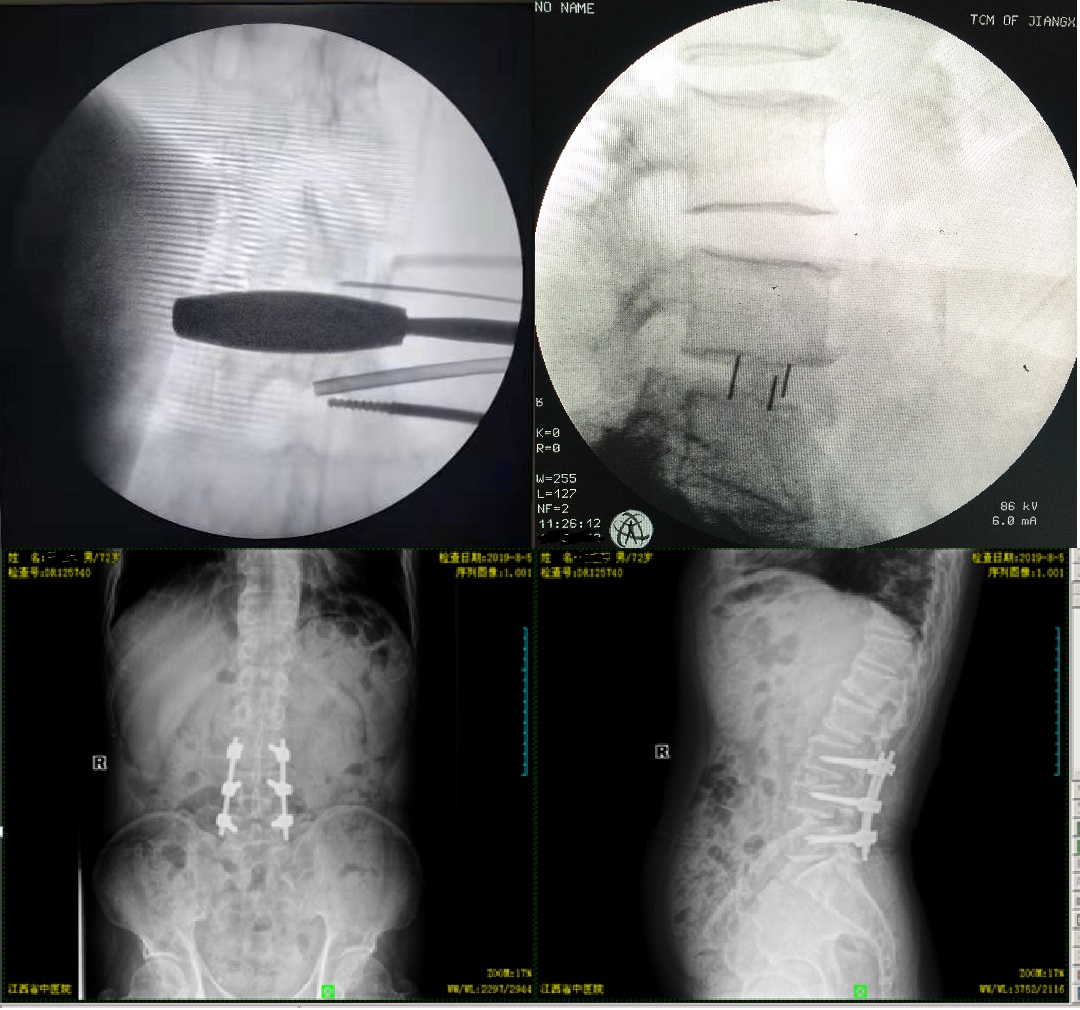

金瓶梅电影 采用先进的“斜外侧椎间融合术”,又称为OLIF技术,是指腰椎侧前方融合技术,与传统后路或前路融合技术相比,它具有更小的创伤、更短的手术时间以及更快的恢复等优势,能避免损伤腰大肌及神经血管。

患者入院后,我科医师立即对患者作出相应处理,以最快的的速度为患者制定了手术方案,由徐王兵主任医师主刀,为患者在全麻下行“椎管减压植骨融合+脊柱内定术”。手术当天,在大家齐心协力努力之下,整个手术非常顺利,术后患者疼痛明显减轻,且切口比传统手术明显缩小,因为保留了腰大肌及软组织,患者术后3天可下床活动,1周内可出院回家,极大的缩短了患者的手术时间和住院时间,且降低了患者的术后疼痛及并发症的发生率。